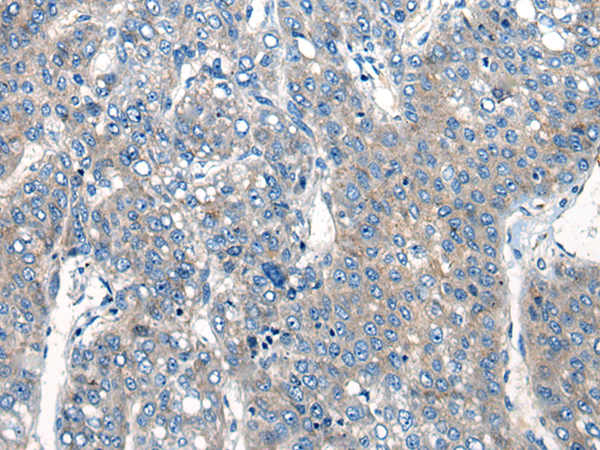

分类: 科研抗体货号: P06279别名:应用: WB,IHC反应种属: Human, Mouse, Rat

分类: 科研抗体货号: P06217别名: NEM7应用: WB,IHC反应种属: Human, Mouse, Rat

分类: 科研抗体货号: P06266别名: NCBP; Sto1; CBP80应用: WB,IHC反应种属: Human, Mouse, Rat

分类: 科研抗体货号: P06210别名:应用: WB,IHC反应种属: Human, Mouse, Rat

分类: 科研抗体货号: P06263别名: CML3; NACED; NAT8-LIKE应用: WB,IHC反应种属: Human, Mouse, Rat

分类: 科研抗体货号: P06205别名: CACC; GOB5; CACC1; CLCRG1; CaCC-1; hCLCA1; hCaCC-1应用: IHC反应种属: Human

分类: 科研抗体货号: P06262别名: DNAS1L2应用: IHC反应种属: Human, Mouse

分类: 科研抗体货号: P06202别名: AMY; CLAC; CLACP; CFEOM5; CLAC-P应用: WB,IHC反应种属: Human, Mouse

分类: 科研抗体货号: P06261别名: DCR2; CD264; TRUNDD; TRAILR4; TRAIL-R4应用: WB,IHC反应种属: Human